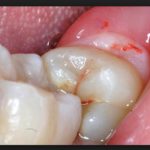

Хорошо, если рост моляров проходит без проблем – такое тоже часто встречается. Но часто, когда лезет зуб мудрости, десна опухает или формируется в капюшон над резцом. Под мягкими тканями скапливается инфекция, и возникает перикоронатит с накоплением гноя. Капюшон разрезают, очищают, часто сразу удаляют резец, потому что в будущем ситуация повторится. Иногда один из моляров давит на лицевой нерв, что вызывает сильные боли, отдающие в голову или ухо, охватывающие часть лица. Это происходит из-за индивидуальных особенностей прорезывания «восьмерок».

Многие стоматологи рекомендуют сразу избавляться от моляров, потому что за ними трудно ухаживать. Щеткой их практически не достать, в этой отдаленной области скапливается грязь. Сначала портятся моляры, а потом инфекция переходит на «семерки», вызывая кариес или периодонтит. Поскольку эти резцы не принимают участие в жевании, их отсутствие никак не отразится на качестве жизни. Если лезет зуб мудрости так, что постоянно травмирует слизистые оболочки, его лучше удалить, потому что в рану неизбежно попадет инфекция, вызывав заражение.

Еще одна причина для хирургического вмешательства – разрушение «семерок». Если лезет зуб мудрости, болит десна, то боль возникает не от моляра, а из-за его «соседа». Именно в «семерку» он упирается, постоянное давление приводит к разрушению эмали, что провоцирует кариес. Без лечения он переходит в пульпит, периодонтит. Поэтому если лезет зуб мудрости, опухла десна рядом, ощущается сдавливание в области соседних резцов, в будущем это приведет к болезням, избежать которых поможет операция.